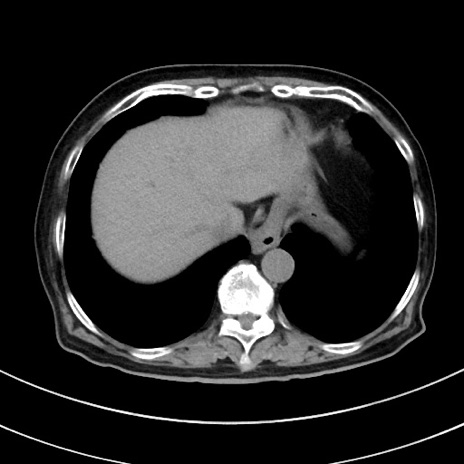

症例33(横断像)

【症例】70歳代 女性

【主訴】心窩部痛

【現病歴】延髄病変の精査・加療にて神経内科入院中。本日より心窩部痛あり。

【身体所見】右下腹部を中心に圧痛と反跳痛あり。

【データ】WBC 10900、CRP 0.02